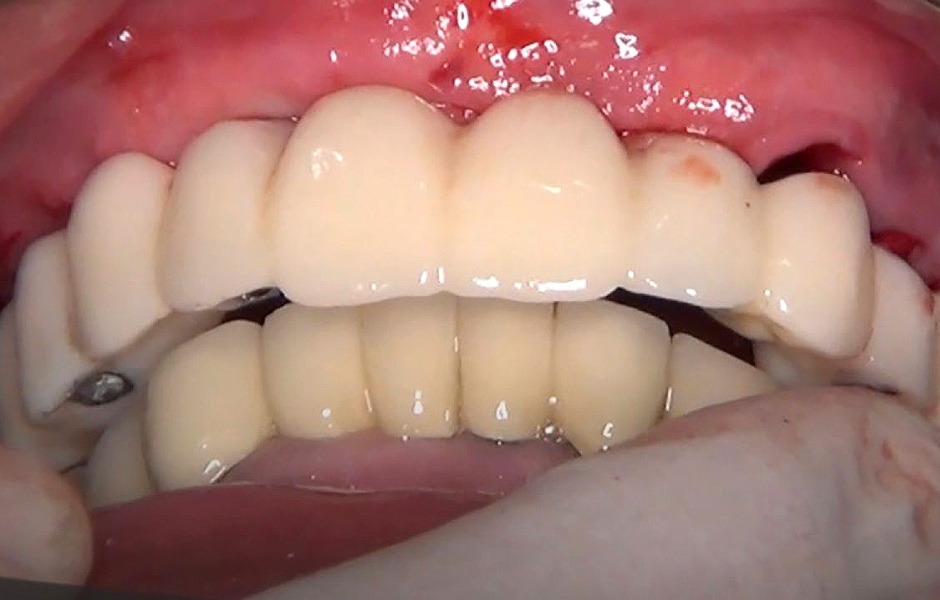

Během kontrolních návštěv pacient vykazoval výborné hojení bez pooperačních komplikací. Provizorní náhrada poskytovala optimální stabilitu a přesnost dosedu, což přispělo ke komfortu a funkčnosti provizorního protetického ošetření (obr. 44).

Definitivní náhrada byla nasazena a ověřena z hlediska estetiky, okluze a funkce (obr. 51–55). Panoramatický kontrolní snímek potvrdil, že všechny parametry protetického ošetření odpovídají očekávaným hodnotám (obr. 56).

Při kontrole po 18 měsících po dokončení ošetření bylo provedeno intraorální, extraorální a radiografické vyšetření. Nebyly zjištěny žádné patologické nálezy a výsledné parametry zůstaly stabilní (obr. 57–62).

Obr. 44

Obr. 51

Obr. 52

Obr. 53

Obr. 54

Obr. 55